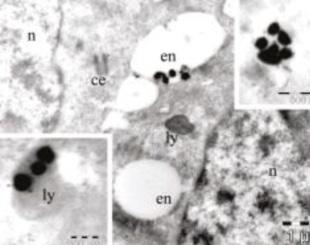

Fig. 8 Organul corti-prelevat de la animale-imagine de microscopie electronică

Fig. 9 Imagine de microscopie elecronică-se văd nanoparticulele de AgNO3 pătrunse în celulele de ureche internă recoltate de la animale viabile în culturi celulare

Fig.10 Imagine de microscopie elecronică-se văd nanoparticulele de AgNO3 pătrunse în celulele de ureche internă recoltate de la animale viabile în culturi celulare

(Fig. 7, 8) S-au studiat anumite substanțe otoprotectoare pe celulele organului Corti, diferiți antioxidanți, iar mai recent posibilitatea utilizării nanomaterialelor de Au și Ag folosite ca și vectori pentru anumite substanțe terapeutice, având ca țintă celulele urechii interne.

(Fig. 9) Toate aceste proiecte de cercetare au putut fi finalizate datorită echipei de cercetare multidisciplinare pe care am constituit o cu alte departamente din cadrul facultății noastre, precum și cu